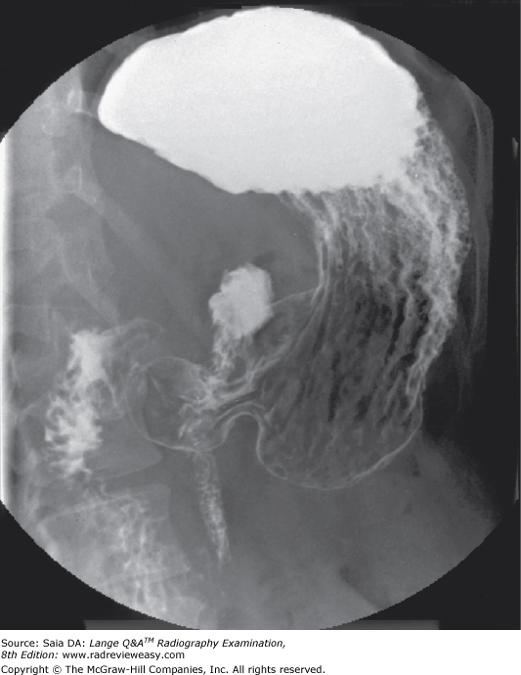

In which of the following positions was the radiograph in Figure A taken?

A RPO

B LPO

C AP axial

D Right lateral decubitus

-The pictured radiograph is an oblique position of the large bowel, illustrating an "open" view of the hepatic/right colic flexure and ascending colon, with the splenic/left colic flexure superimposed on the descending colon. Therefore, the radiograph must have been made in either an RAO (if the patient was prone) or an LPO (if the patient was supine) position. The LAO and RPO positions are used to demonstrate the splenic/left colic flexure and descending colon free of self-superimposition. AP or PA axial is generally used to visualize the rectosigmoid colon.